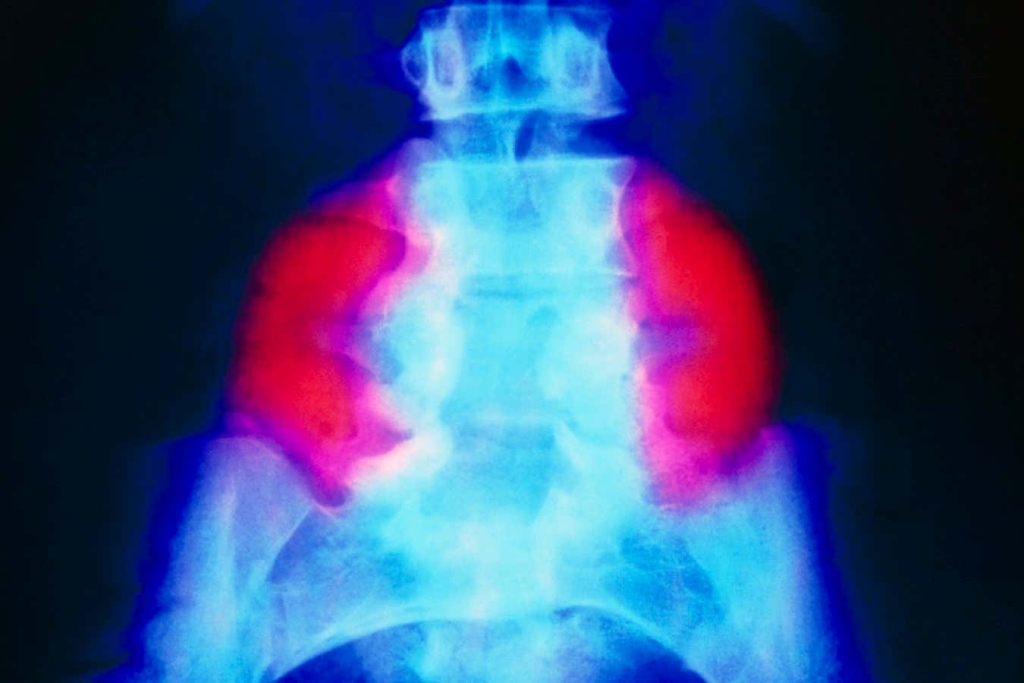

One of the most significant findings from the trial relates to a common complication called hindbrain herniation, which affected all six fetuses at the time of surgery. This condition occurs when excess fluid accumulates in the skull, forcing the cerebellum (the brain’s coordination center) to protrude through a hole at the base of the skull. While standard surgical intervention often helps reduce this herniation, many children still experience ongoing neurological complications.

The results from the stem cell patch trial are remarkable: MRI scans performed after birth showed complete reversal of hindbrain herniation in all six babies. Additionally, the surgical sites healed beautifully with no evidence of abnormal cell growth—a critical concern given the powerful regenerative properties of stem cells. “A key worry was that adding stem cells in a fetus would make the cells grow like crazy, but we didn’t see that,” notes Dr. Farmer.